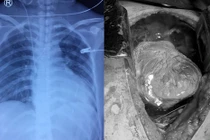

Thông tin từ Khoa Phẫu thuật Tim mạch – Lồng ngực, Bệnh viện đa khoa tỉnh Phú Thọ cho biết, người bệnh bị kéo đâm trúng ngực trái, được đưa vào cấp cứu tại Trung tâm Y tế huyện Cẩm Khê. Tại đây, người bệnh khó thở, mạch nhanh, huyết áp tụt, được xử trí cấp cứu truyền dịch, thở oxy, được chụp CT ngực, siêu âm tim phát hiện có tràn máu màng tim.

Ngay lập tức, các bác sĩ đã hội chẩn trực tuyến với các bác sĩ khoa Phẫu thuật Tim mạch – Lồng ngực, Bệnh viện đa khoa tỉnh Phú Thọ. Chẩn đoán được đưa ra là vết thương tim. Người bệnh được duy trì hồi sức và vận chuyển nhanh chóng đến Bệnh viện đa khoa tỉnh Phú Thọ.

Người bệnh được chuyển đến Bệnh viện đa khoa tỉnh Phú Thọ trong tình trạng khó thở nhiều, da xanh nhợt, mạch khó bắt, huyết áp 90/60mmHg, vết thương thành ngực trái ngang mức khoang liên sườn 5, kích thước 2cm, tiếng tim mờ. Siêu âm cấp cứu tại giường có nhiều dịch máu trong màng tim và màng phổi trái, người bệnh được tiến hành các biện pháp hồi sức và được chỉ định phẫu thuật cấp cứu.

Trong phẫu thuật, các bác sĩ thấy trong khoang màng tim có rất nhiều máu đỏ tươi, khoang màng phổi có 400ml dịch máu đỏ, vết thương rách màng tim thấu vào cơ tim ngay sát động mạch vành phải đã được máu cục bịt lại không còn chảy máu nữa. Các bác sĩ đã lấy máu cục và khâu kín vết thương cơ tim.

Ca phẫu thuật diễn ra trong 2 tiếng, trong phẫu thuật phải truyền 1050ml máu và 600ml huyết tương. Sau phẫu thuật ngày thứ 2, người bệnh đã ổn định và đi lại được.